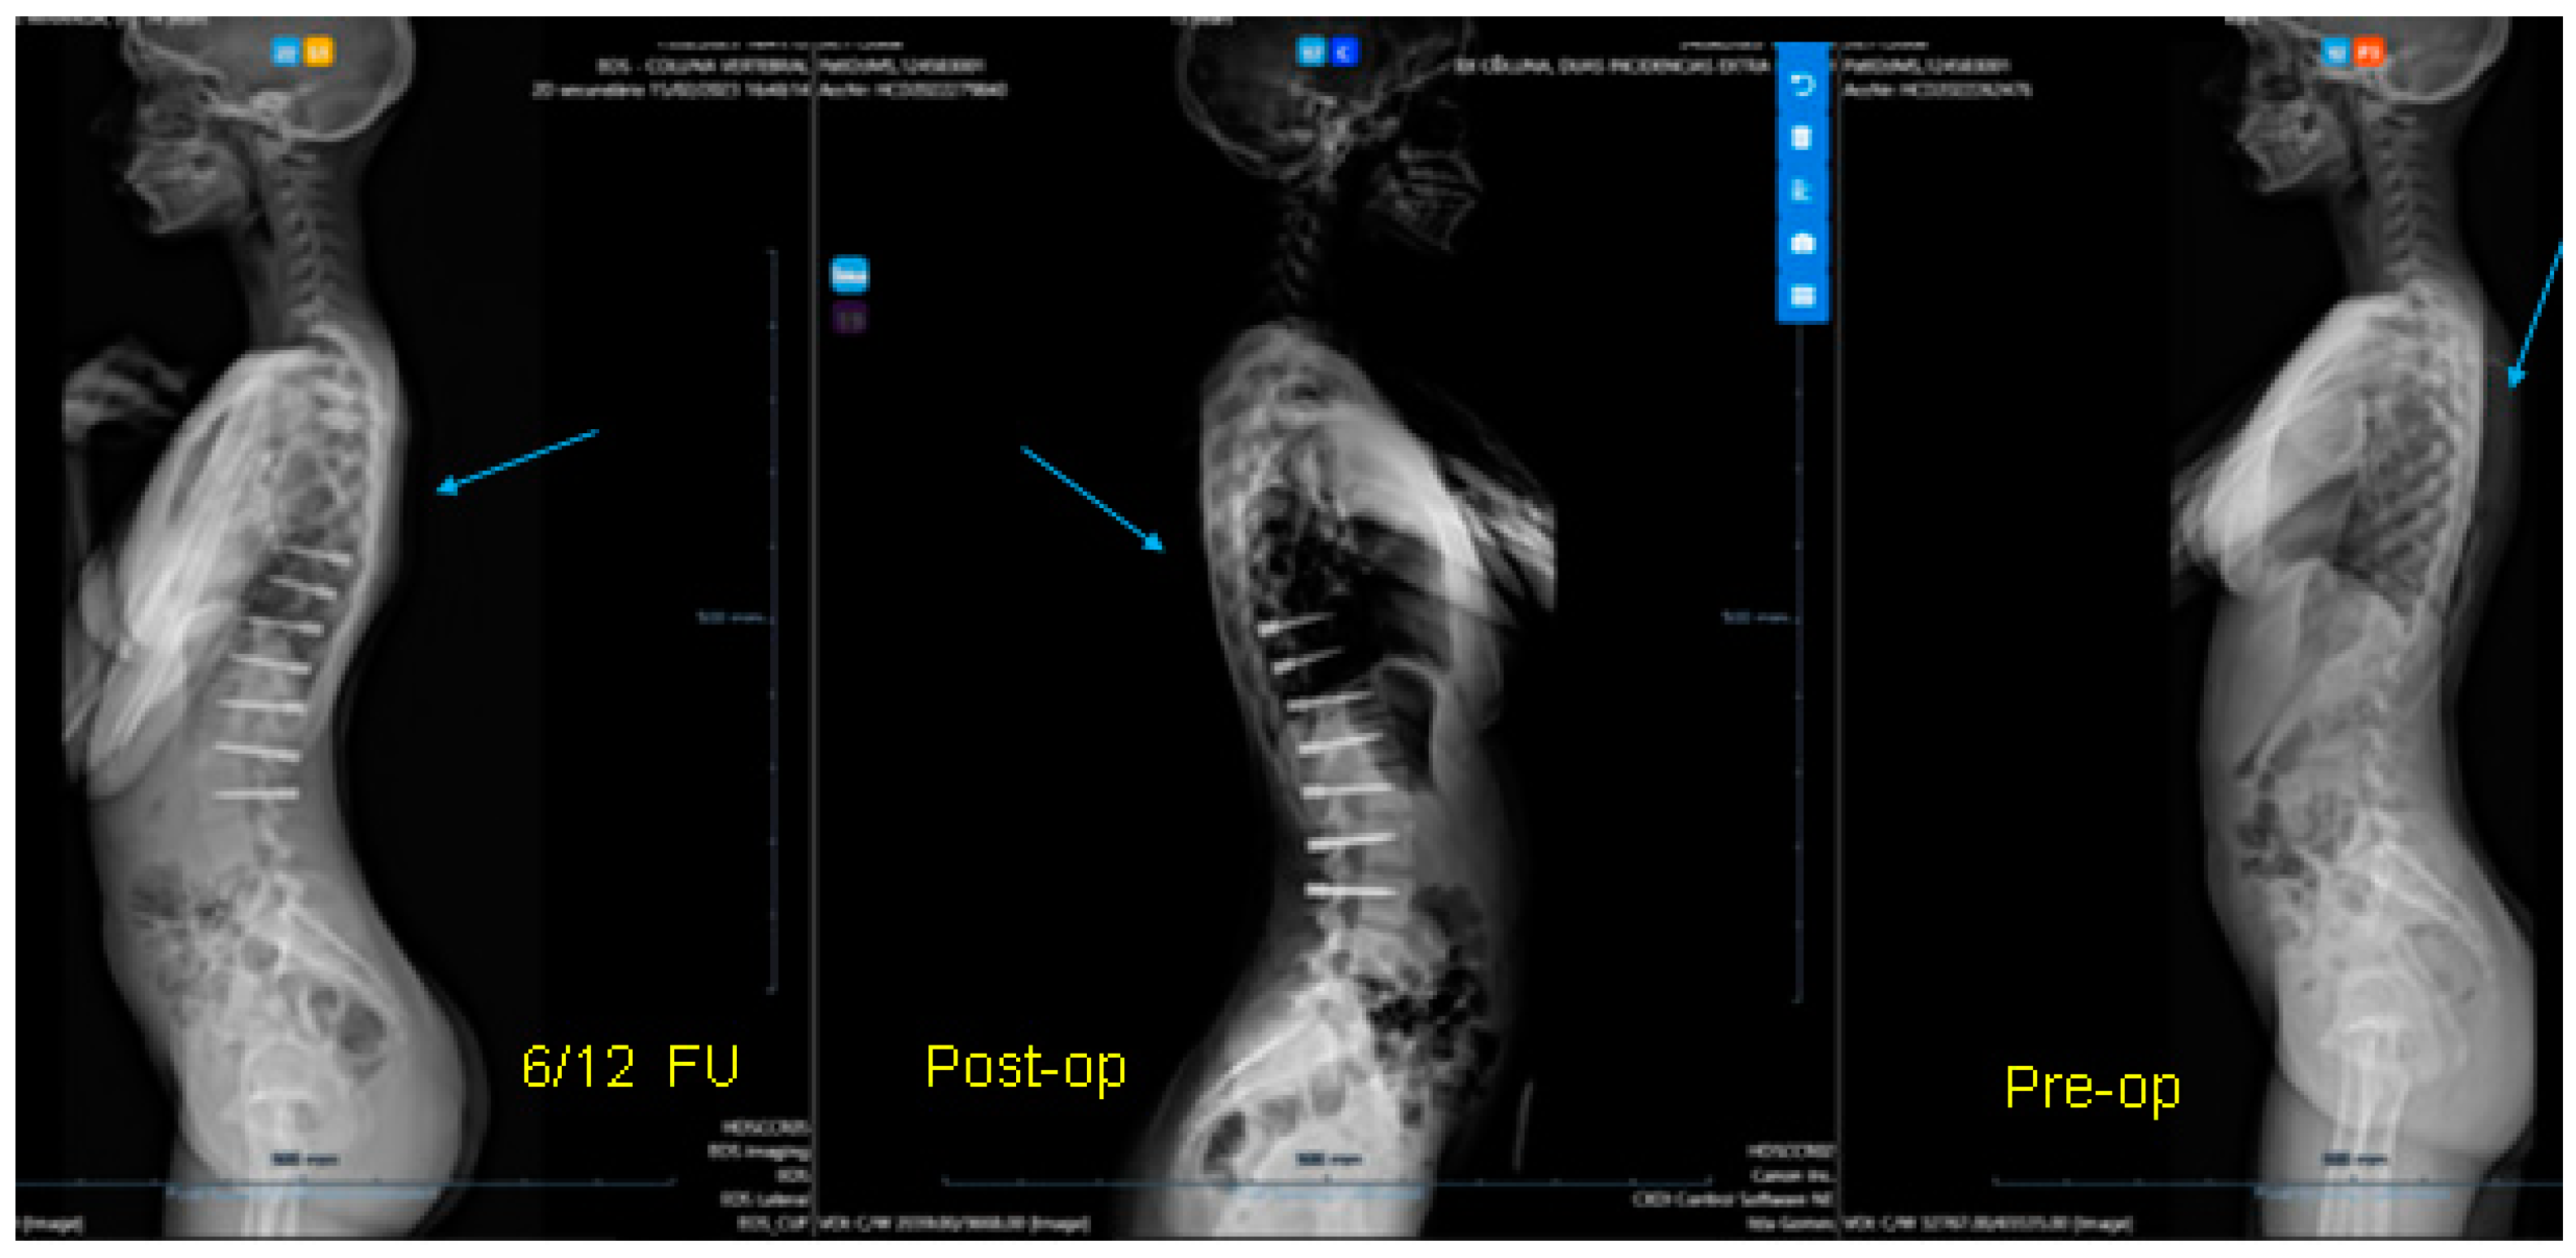

Figure 9.

Over-correction. (A) Pre-op (left) + 18-month FU (curvature apex corrects to the opposite side) (right). (B) Post tether release. (C) Immediate post-op erect radiograph.

3.1. Complications

The only case with a 15-month follow up progressed to coronal over-correction and had to be revised (under local anaesthetic) for tether release at four levels (Figure 9A,B). Since then, she has been doing well clinically and radiologically. This complication may have happened because correction obtained at the index procedure was too much, with a Cobb angle of 13.6° in the immediate post-operative erect radiograph (pre-op Cobb angle 56.7°) in a girl rated Sanders 3 (Figure 9C).